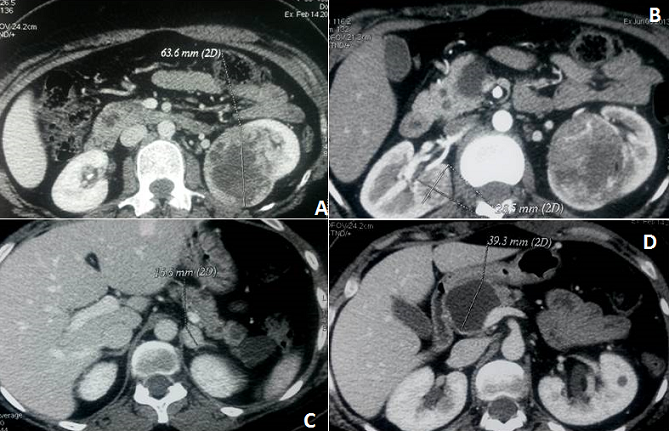

La maladie de Von Hippel-Lindau (VHL) est un syndrome familial rare autosomique dominant associé à des tumeurs malignes ou bénignes surtout des hémangioblastomes rétiniens, cérébelleux, de la moelle épinière, carcinomes à cellules rénales ou phéochromocytomes. Nous rapportons le cas d'une patiente âgée de 35 ans sans antécédents notables, issue d'un mariage non consanguin qui rapporte des douleurs abdominales isolées. L'examen clinique notait une protéinurie à 1+ aux bandelettes urinaires, 2 tâches café au lait centimétriques au niveau de l,abdomen et du cou et une douleur lombaire droite. L,examen neurologique était normal. Il n'y avait pas d'HTA. La biologie notait un SIB. Le scanner abdominal a montré un pancréas siège de multiples masses kystiques intra-glandulaires diffuses dont la plus volumineuse siège en céphalo-isthmique refoulant le cadre duodénal et venant au contact sans envahissement du tronc spléno-mésaraique. Le rein droit est le siège d'une masse tissulaire médio-rénale de 21 mm, se rehaussant de façon hétérogène sans infiltration de la graisse péri rénale. Le rein gauche est le siège de deux masses tissulaires médio-rénale et polaire inférieure de 18*63 mm. Nodule surrénalien gauche spontanément isodense, prenant le contraste et mesurant 17*15 mm. Une phacomatose de VHL était évoquée devant: les masses rénales, les lésions pancréatiques et le nodule surrénalien. L'IRM cérébro-médullaire, le fond d’œil et l'angiographie rétinienne étaient normaux. L'étude génétique a mis en évidence une mutation située sur l'exon 1 du gène VHL. La patiente a eu une tumorectomie droite et une néphrectomie gauche concluant à un carcinome à cellules claires du rein ce qui confortait le diagnostic. Le recul actuel est de 10 mois.